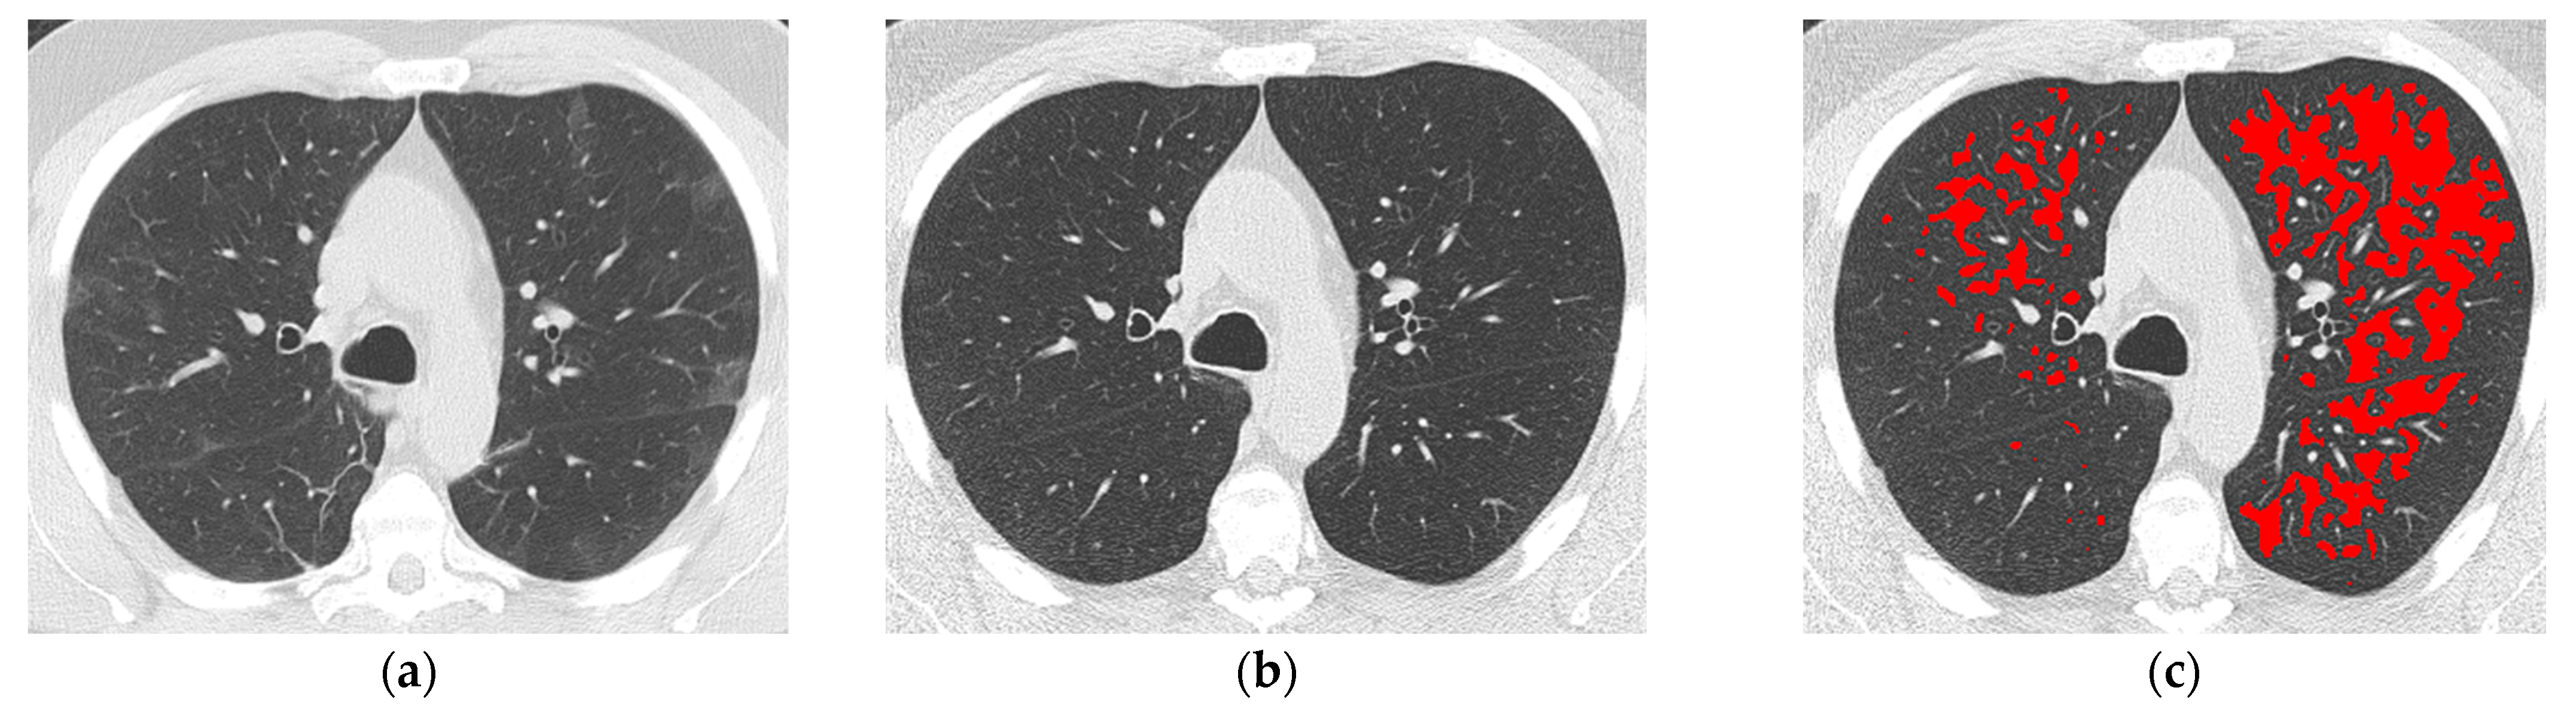

2.2. Chest CT Acquisition and Interpretation

3.2. CT Assessment